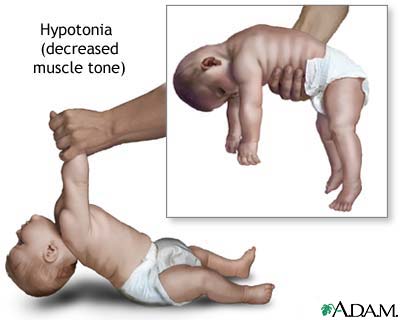

- Infant botulism can happen if the spores of the bacteria get into an infant’s intestines. The spores grow and produce the toxin which causes illness.

The disease begins with weakness, blurred vision, feeling tired, and trouble speaking. This may then be followed by weakness of the arms, chest muscles, and legs. The toxin attacks the body’s nerves and causes difficulty breathing, muscle paralysis, and even death.

Vomiting, swelling of the abdomen, and diarrhea may also occur. The disease does not usually affect consciousness or cause a fever.

Infant botulism typically has no long-term side effects but can be complicated by treatment associated adverse events. The case fatility rate is less than 1% for hospitalized babies.

infant botulism: https://www.tamingthesru.com/blog/annals-of-b-pod/b-pod-cases/infantile-botulism